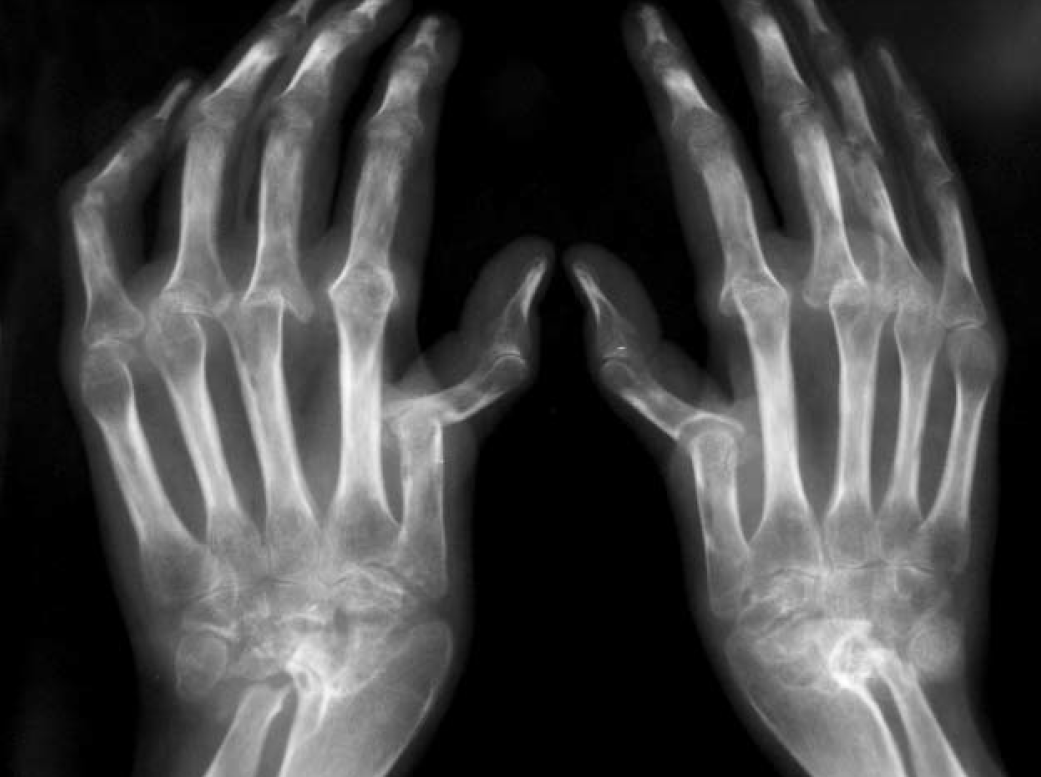

Поздняя стадия ревматоидного артрита. Без адекватного лечения видим такую картину.